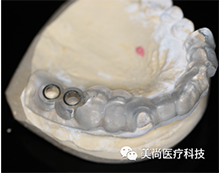

放射导板:

放射导板又称扫描义齿、放射义齿,是包涵了种植修复信息的带有放射标记点的活动义齿。它包涵了将来种植修复体的理想位置,使得医生在做术前设计时不仅考虑牙槽骨的情况,同时也考虑修复体的位置,以获得最佳的生物力学和美学效果。

安插多个放射阻射点(放射导板基托必须保证没有金属)

放入阻射物

• 阻射物必须突出基托表面0.5-1mm,去除干净周边粘接剂

• 用球钻在基托表面定位时,切勿穿透至组织面,切勿破坏组织面完整性

咬合稳定、就位准确、进行CT拍摄

放射导板展示图

放射导板